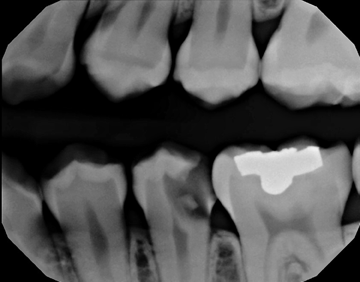

When a member of my front office staff, Yari, confided in me that she had a toothache, I took a bitewing radiograph (DEXIS™ Platinum) and discovered that she had deep distal decay on tooth #20. Intraoral examination revealed a fracture beyond the cervical extent of the tooth (Fig. 1). The tooth was non-restorable, so she was facing extraction and had several choices about how to replace that tooth. We discussed the possibility of a removable partial denture, a fixed bridge, or an implant.

Fig. 1 Fig. 2

To start the process, we took an i-CAT CBCT at 16cm x 11cm as a 0.25 voxel size (Fig. 2). I chose a full field of view size because Yari had some dental issues on the lower right-hand side to check as well, so I needed to have additional information on that area.